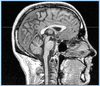

Boston Children's Hospital in Waltham is seeking participants for a paid brain MRI study seeking to understand concussions and migraines.

Researchers at the Boston Children’s Hospital in Waltham are seeking kids, teens, and young adults to participate in ongoing brain imaging studies to help understand how concussions and migraines change brain activity.